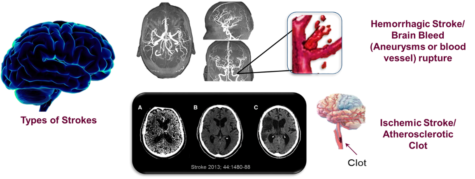

All strokes are not alike, they include ischemic, hemorrhagic, and transient ischemic attacks (TIA). Although older persons are thought to be the primary risk group for strokes, children and fetus can potentially be included in the risk population. The most common type is ischemic stroke caused by clots occluding the blood flow to the brain. The clots can be from congenital heart defects, sickle cell disease, and trauma that injures a large artery; however, they can also be a consequence of high cholesterol, oxLDL, and blood clots as well as exogenous and endogenous toxins. The foam cells in the artery can be either a stable plaque (solid fibrous extracellular tissue with small amounts of lipid) or vulnerable plaque (consist of macrophages and lipids in the artery wall that erosion prone). These “culprit” plaques are the cause of disruption in blood flow that leads to vascular events such as heart attacks and strokes. Hemorrhagic strokes are due to a rupture in the blood vessel that bleeds to the deep tissue of the brain; often caused by hypertension, but also aging vessels, arteriovenous malformations (cluster of deformed blood vessels), and aneurysms (a balloon of blood in the artery). Intracerebral hemorrhages are the most common type due to the prevalence of high blood pressure but can also be caused by exogenous toxins such as smoking, oral contraceptives with high estrogen, alcohol, and illegal drugs. TIAs often called mini-strokes, produce symptoms similar to those of stroke but without the lasting effects. They are thought to be warning signs to an ischemic stroke; the clots that cause them may be resolved without treatment, but without treatment they can lead to further strokes or death.